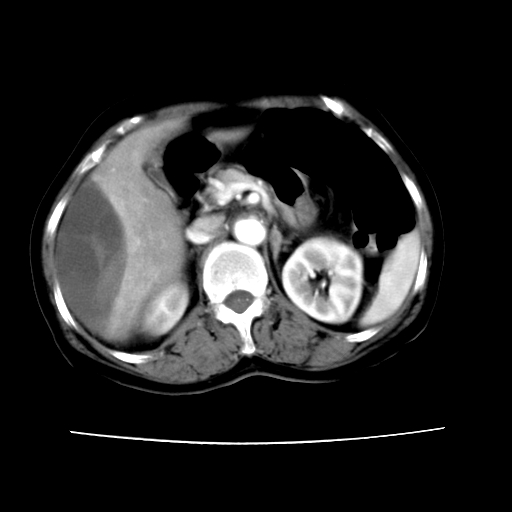

ct增强

考虑肝腺瘤出血可能,肝血管瘤增强表现不是很典型,放在第二。

6月份ct片显示肝内巨大混杂密度团块,伴包膜下积液(内含液液平面),增强多无明显强化。只能考虑肝占位病变,并肝内、血膜下血肿。肝ca并出血多见,而肝血管瘤并破裂出血少见。

6月份ct片显示肝内巨大混杂密度团块,伴包膜下积液(内含液液平面),增强多无明显强化。只能考虑肝占位病变,并肝内、包膜下血肿。肝ca并出血多见,而肝血管瘤并破裂出血少见。

从平扫+增强及治疗后复查片,病变明显缩小,不考虑肝癌出血可能,还是考虑为良性病变可能性大;单纯血肿并包膜下积液吧,病变强化没法解释,肝血管破裂出血吧,增强不符合典型血管瘤的表现,良性肿瘤破裂出血吧,复查片看来好像也不太支持(没做强化也不太好说)。本人还是考虑单纯肝内血肿并包膜下积液,强化是不是血管有外渗。